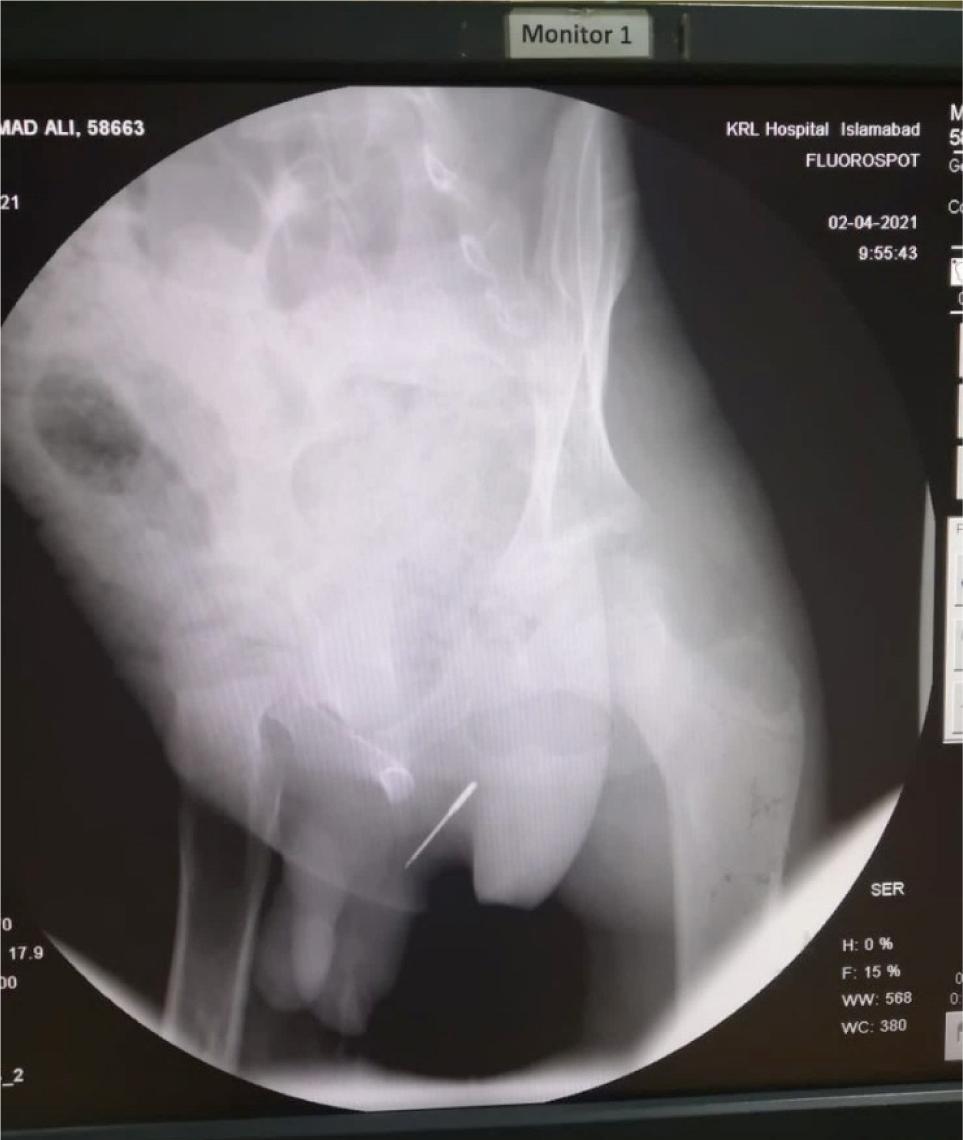

An 11-year-old boy presented in the paediatric out-patient department of KRL Hospital Islamabad with poor urine flow, weak stream, and pain in pubic region for 3 weeks. The attending physician examined the patient and upon a detailed examination, genitourinary tract stricture was suspected. The patient was referred to the department of urology. The urologist ordered retrograde urethrography (RUG) to investigate the cause of urinary retention. The RUG showed a thin sharp opaque in the urethra. A sharp needle at the posterior urethra was found along with an incidental finding that is, fracture of the inferior ramus of pubis (Figures 1 and 2). Hence, foreign body urethra was diagnosed.

Figure 2: Plain X-ray showing opaque foreign body.